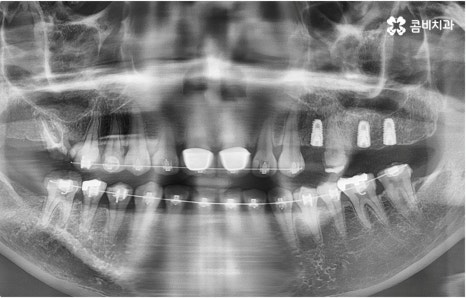

자연 치아를 살리기 위한 거의 마지막 단계의 보존 치료가 바로 신경치료, 재신경치료, 치근단절제술 등이며, 만약 치아재식술을 통해서도 살릴 수 없을 정도로 손상이 깊고 심하다면 해당 치아를 발치하고 임플란트를 통해 인공 치아로 대체해 줄 필요가 있습니다.

임플란트는 유치, 영구치 이후로 제 3의 치아라고 불리울 만큼 자연 치아의 상실에 대처하는 인공 치아 중에 가장 각광을 받고 있습니다. 저작력 회복이 80%에 가깝고 심미적으로 자신의 치아와 거의 다름없어 보이는 부분에서도 만족도가 높아 많은 분들이 찾고 있지만 식립 성공률과 안정적인 지속률에 크게 영향을 주는 올바른 위치 및 각도로의 식립을 무리하지 않게 진행하기 위해 술자의 높은 숙련도를 요하는 고난도의 수술이기 때문에 임상 경험이 많고 뛰어난 노하우를 갖추고 있는 담당의 선생님과 함께 하시는 것이 중요한 포인트라고 할 수 있어요.

환자분들의 상황에 따라 하루 만에 식립 및 임시 치아 장착까지 끝나서 바로 식사를 할 수 있는 원데이 임플란트 과정, 정밀 검사 후 디지털 장비를 이용하여 모의 수술 후 맞춤 가이드를 따라 무절개 / 최소절개 수술을 진행하는 네비게이션 임플란트 과정 등 관련 기술이 점점 더 섬세하게 발달하고 있어서 보다 편안한 이용이 가능하게 된 것은 사실이지만 본래 자신의 치아보다 좋은 인공 치아는 없을 것이기 때문에 건강할 때 이를 잘 유지 관리하고 구강 질환이 발생했을 때는 되도록 빠르게 이에 대처하실 필요가 있어요.